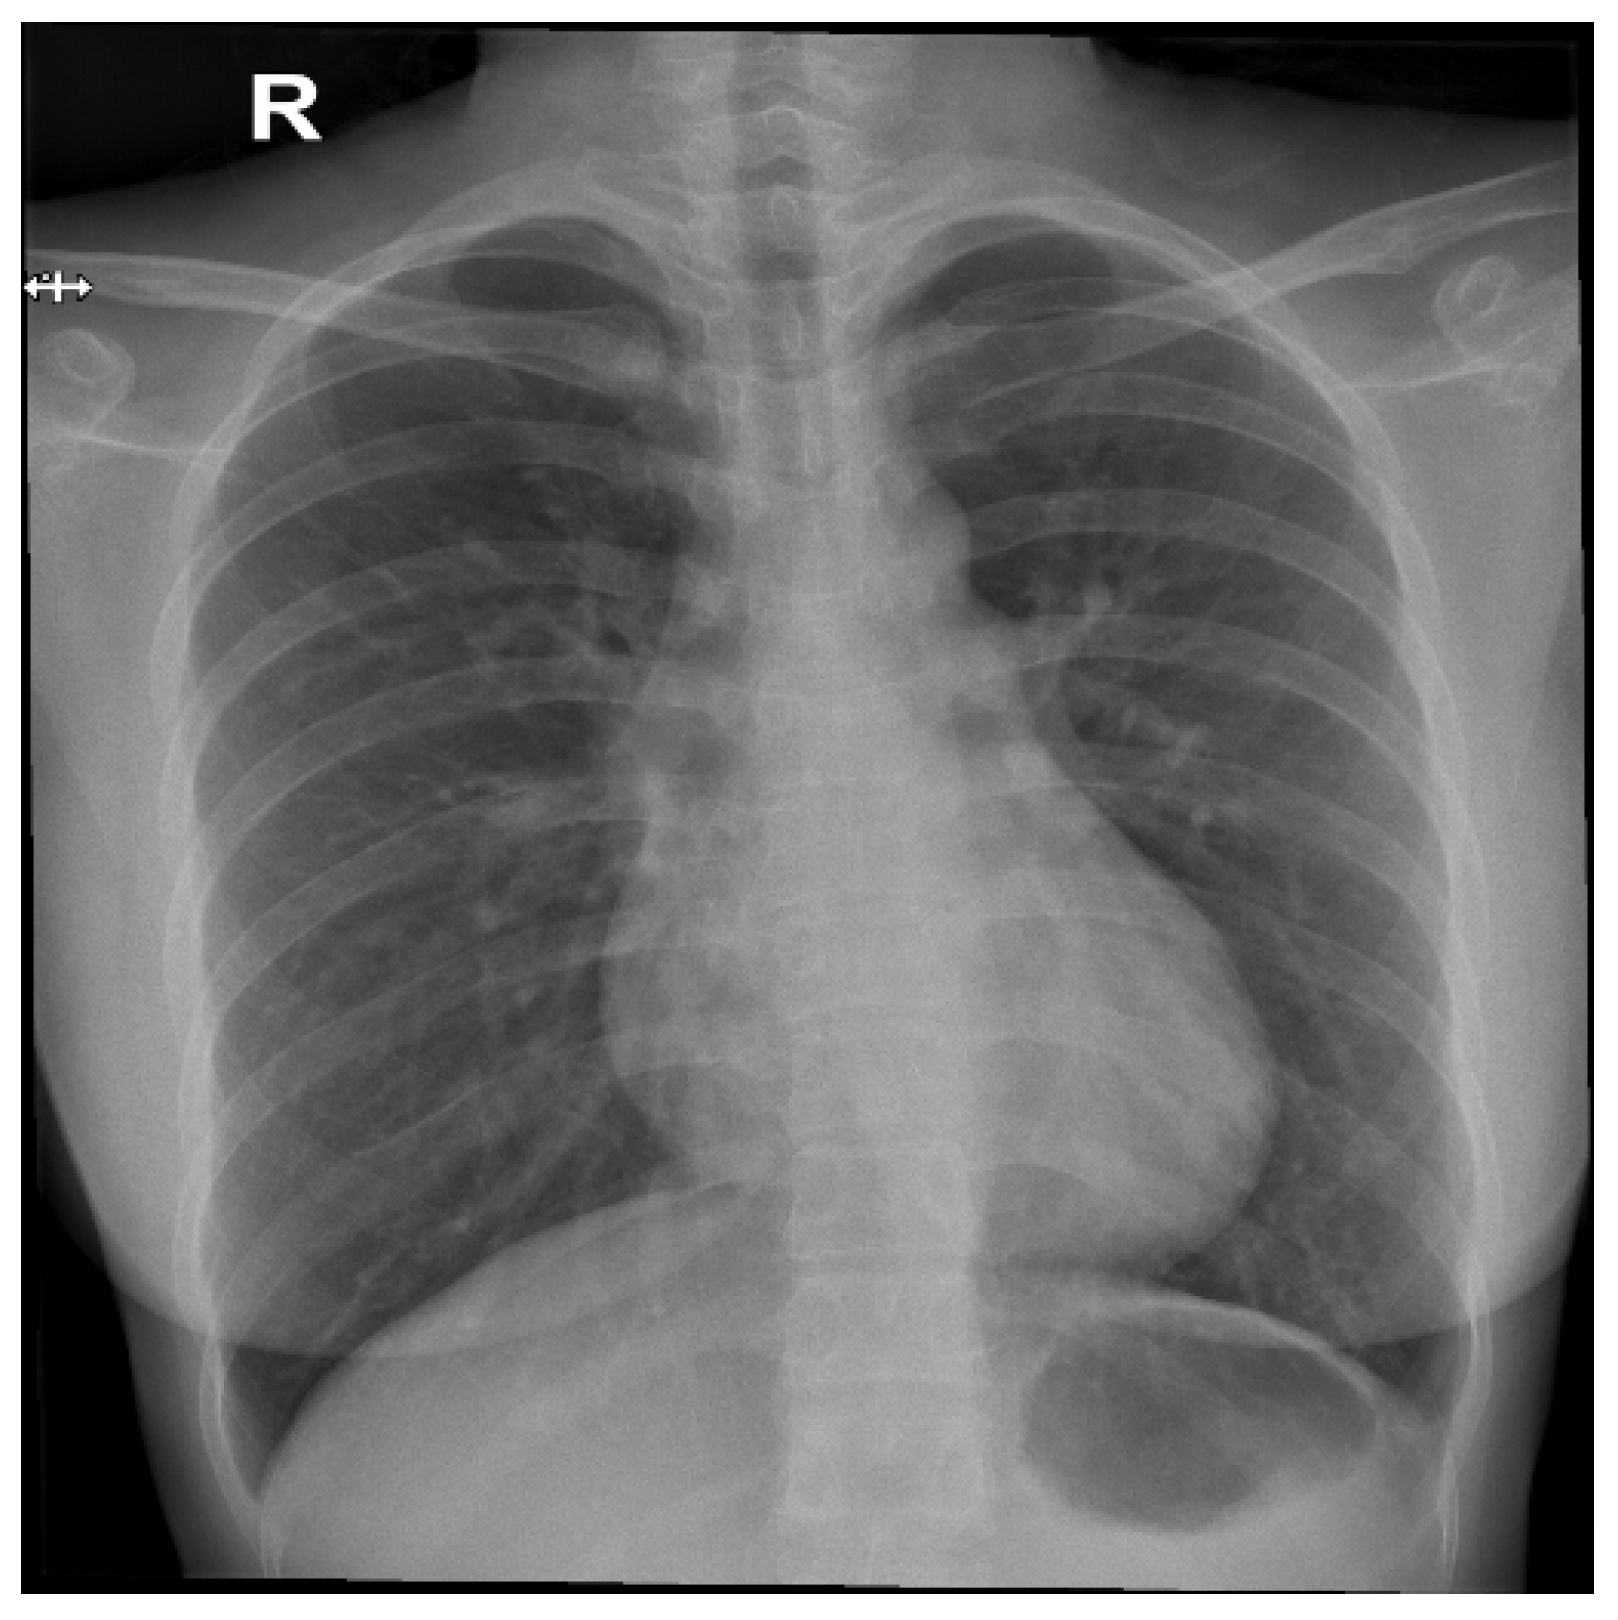

From a visual perspective, as illustrated in the comparison images above, both the RSCM as in Figure 1 and NIH as in Figure 2 datasets exhibit comparable quality in terms of resolution, clarity, and diagnostic relevance. This similarity ensures that image quality does not introduce any significant bias or variation.

Figure 1.

Sample image from the RSCM dataset. R: Right.